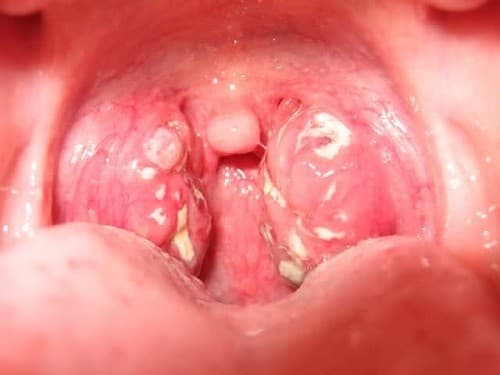

Với cấu trúc vòm họng được phân chia thành nhiều hốc, ngăn, vi khuẩn, nên amidan dễ dàng bị vi khuẩn xâm nhập, lâu ngày tạo nên các khối mủ bã đậu và vón cục. Đồng thời với sự cọ xát của thức ăn khi đi qua thành họng, các kém mủ trong hốc amidan bị bật ra. Mủ có hình dạng như hạt tấm, có màu trắng xanh và mùi hôi.

Viêm amidan hốc mủ là bệnh lý nguy hiểm cần phải điều trị sớm

Cũng giống như bạn, nhiều cũng có chung thắc mắc viêm amidan hốc mủ có nguy hiểm không? Đây là bệnh viêm nhiễm nặng cần phải điều trị đúng phương pháp mới cải thiện được tình trạng bệnh, cũng như ngăn ngừa biến chứng.